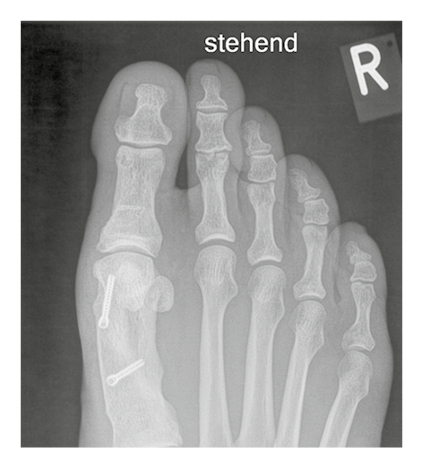

Hallux valgus correction: MAGNEZIX® CS and titanium in a comparison

The x-rays show a hallux valgus on the left foot treated with MAGNEZIX® CS over a period of 1 year post-op. The same procedure was performed on the patient's right foot years earlier with titanium screws which serves as a comparison.